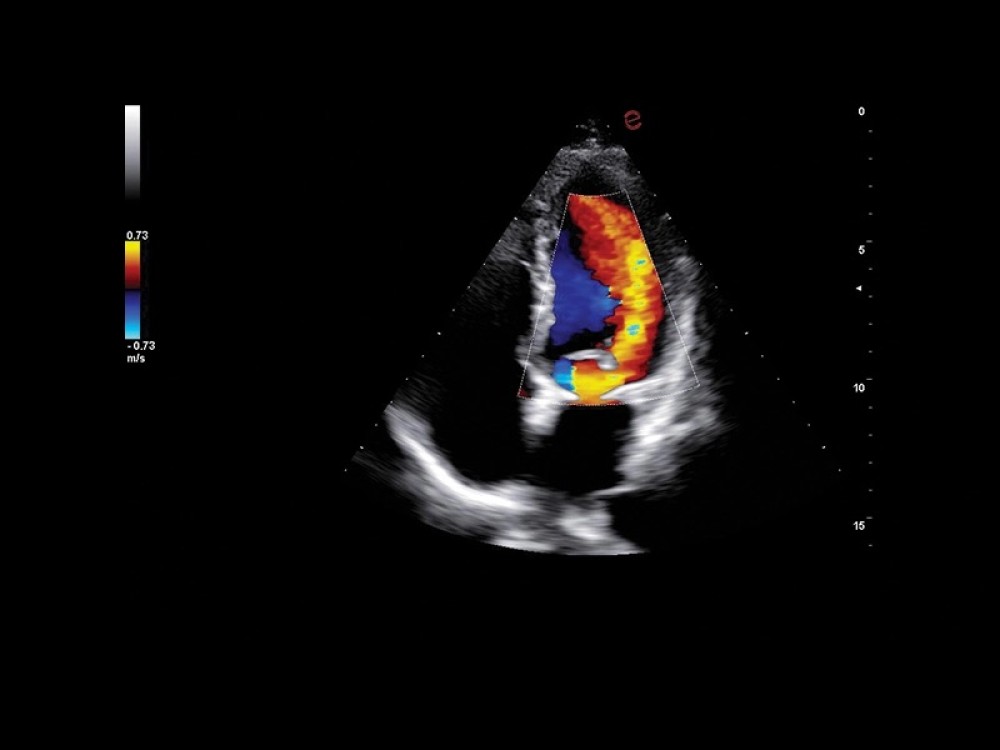

Kardiovaskulyar və Obstetrik AI Paketləri: Avtomatik ölçmələr və strain görüntüləmə vasitəsilə kardiovaskulyar və obstetrik müayinələrdə diaqnostik dəqiqlik artırılır.